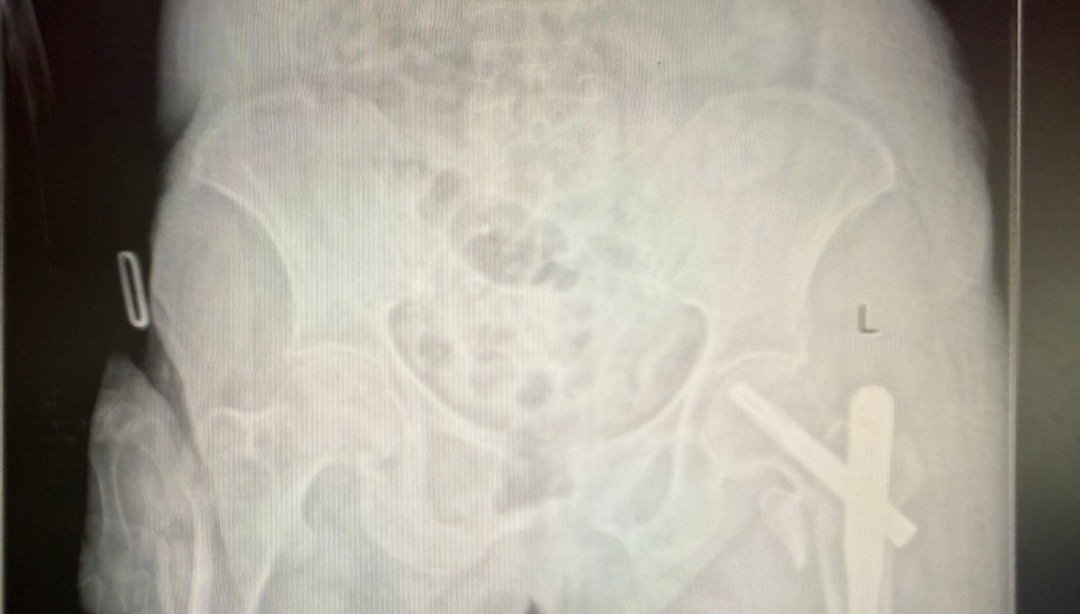

手术当日,杨自权主任团队借助丰富的手术经验,术前在牵引床、G臂辅助下迅速给予患者闭合复位骨折断端,结合经典的“2-1-1”微创手术切口实施手术,手术过程顺利,G臂透视可见骨折复位满意,髓内钉位置满意。术后患者顺利出院,安返家中。

此次近103岁超高龄股骨转子间骨折患者的成功救治,再次彰显了山医大一院骨科在高龄手术领域的实力和担当。今后,骨科将继续秉承以患者为中心的服务理念,不断提高医疗技术水平,继续创造更多的医学奇迹,为患者的健康保驾护航。